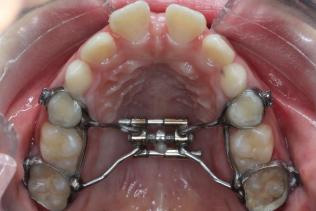

图 1 扩弓器佩戴时

作为常见的矫治方法,上颌扩弓的治疗过程需要小朋友与家长的积极配合, 才能实现满意的治疗效果。下面介绍常用的固定式上颌扩弓器佩戴使用过程中的 注意事项。